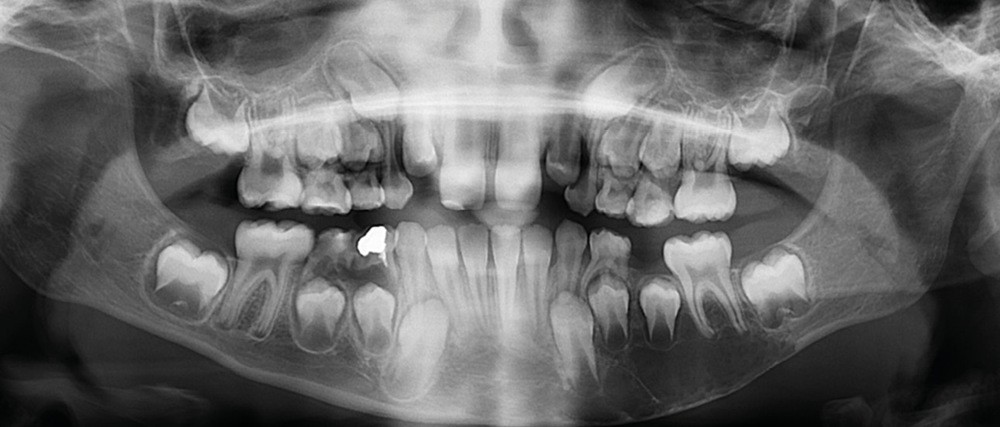

L’évolution clinique lente, la découverte fortuite et les examens radiologiques font évoquer un kyste essentiel (kyste osseux solitaire).

Il existe une zone ostéolytique unique, aux contours extrêmement fins, évidant la branche horizontale de la mandibule, et dont la limite supérieure est mieux marquée et dite « circinée », contournant les racines dentaires.